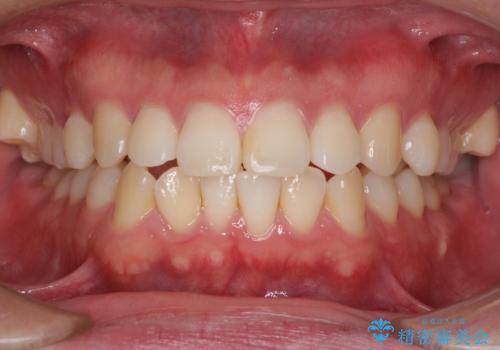

インビザラインで奥歯の咬み合わせと前歯のデコボコを改善

- 前歯のデコボコと奥歯の咬み合わせを気にして来院された患者様です。

前歯のデコボコはインビザラインで十分に対応可能と判断できましたが、咬合力が強いため、臼歯(特に右側)の交叉咬合はインビザライン単体では困難と思われました。

まずはインビザライン単体で矯正治療を開始し、交叉咬合が改善されない場合にはアンカースクリューなどの使用を検討することとしました。

インビザライン単体では右側の交叉咬合を解消することができなかったため、アンカースクリューを併用して咬合を改善させました。